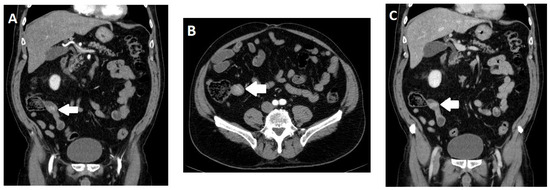

- Morani, A.C.; Gupta, S.; Elsayes, K.M.; Mubarak, A.I.; Khalaf, A.M.; Bhosale, P.R.; Sun, J.; Jensen, C.T.; Kundra, V. Performance of Multidetector Computed Tomography and Negative Versus Positive Enteric Contrast for Evaluation of Gastrointestinal Neuroendocrine Neoplasms. J. Comput. Assist. Tomogr. 2022, 46, 333–343. [Google Scholar] [CrossRef]

- Pilleul, F.; Penigaud, M.; Milot, L.; Saurin, J.C.; Chayvialle, J.A.; Valette, P.J. Possible small-bowel neoplasms: Contrast-enhanced and water-enhanced multidetector CT enteroclysis. Radiology 2006, 241, 796–801. [Google Scholar] [CrossRef]

- Soyer, P.; Dohan, A.; Eveno, C.; Dray, X.; Hamzi, L.; Hoeffel, C.; Kaci, R.; Boudiaf, M. Carcinoid tumors of the small-bowel: Evaluation with 64-section CT-enteroclysis. Eur. J. Radiol. 2013, 82, 943–950. [Google Scholar] [CrossRef]

- Dohan, A.; El Fattach, H.; Barat, M.; Guerrache, Y.; Eveno, C.; Dautry, R.; Mule, S.; Boudiaf, M.; Hoeffel, C.; Soyer, P. Neuroendocrine tumors of the small bowel: Evaluation with MR-enterography. Clin. Imaging 2016, 40, 541–547. [Google Scholar] [CrossRef]